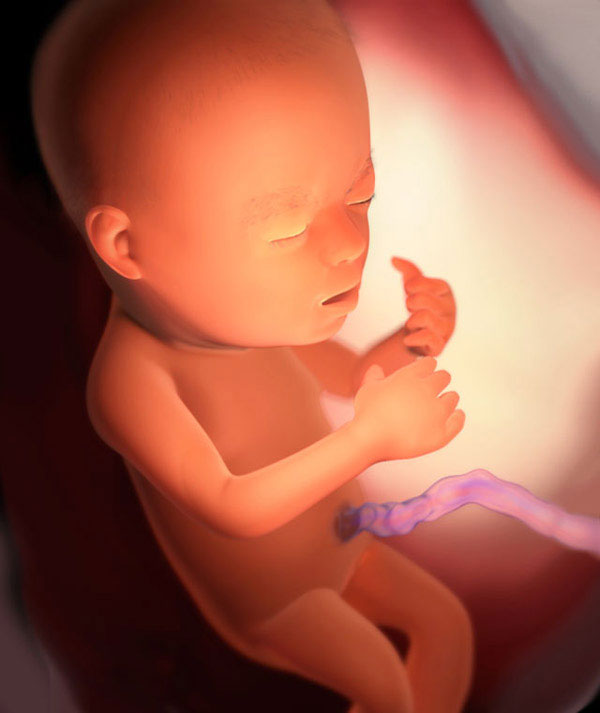

Como o feto se desenvolve

Na 22ª semana, o feto dorme a maior parte do dia. Mas mesmo em um sonho, ele move os braços e as pernas, toca o cordão umbilical e, em geral, tudo o que alcança. A posição do feto no útero muda várias vezes ao dia, mas você não sente nada, a menos que o bebê dê uma forte sacudida ao se mover.

E aqui está o fruto:

Desenvolvimento fetal:

- unhas totalmente formadas começam a crescer;

- as glândulas sudoríparas estão melhorando;

- o número de conexões neurais aumenta;

- em um nariz minúsculo, um septo cartilaginoso se forma;

- a mineralização óssea continua;

- todas as vértebras e discos intervertebrais são totalmente desenvolvidos na coluna vertebral;

- o pâncreas está completamente pronto para o trabalho;

- os olhos do bebê já têm íris, mas ainda não têm pigmento (é por isso que os olhos mudam de cor nos recém-nascidos).